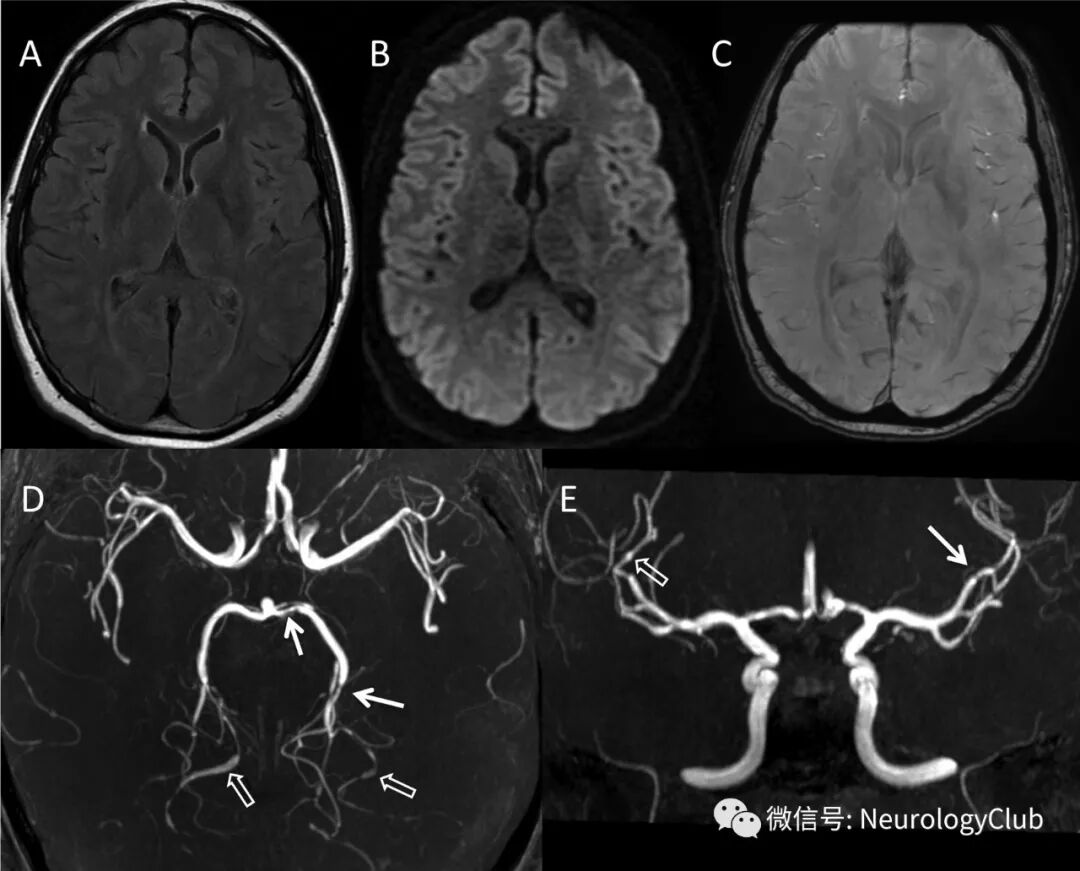

31岁男性,既往有偏头痛病史,表现为突然出现的搏动性头痛和血压升高(190/120mmHg)。自我疼痛评分为10/10。神经系统查体正常。一周前,患者因体育锻炼后出现类似症状而入院,但因头颅CT平扫结果正常出院。本次进一步头颅MRI检查。常规MRI序列,包括T2/FLAIR,DWI和SWI,未发现异常(图)。

(图:A:FLAIR;B:DWI;C:SWI;头颅MRI未见明显异常,排除梗死、出血和可逆性后部脑病综合征;D-E:MRA可见广泛的多发动脉痉挛,主要累及大脑后动脉,呈“串珠样”外观,主要因血管交替性狭窄和扩张所致;大脑前循环,尤其是大脑中动脉同样受累)

MRA可见弥漫性动脉痉挛,呈“串珠”样表现,符合可逆性脑血管收缩综合征(reversible cerebral vasoconstriction syndrome,RCVS)。